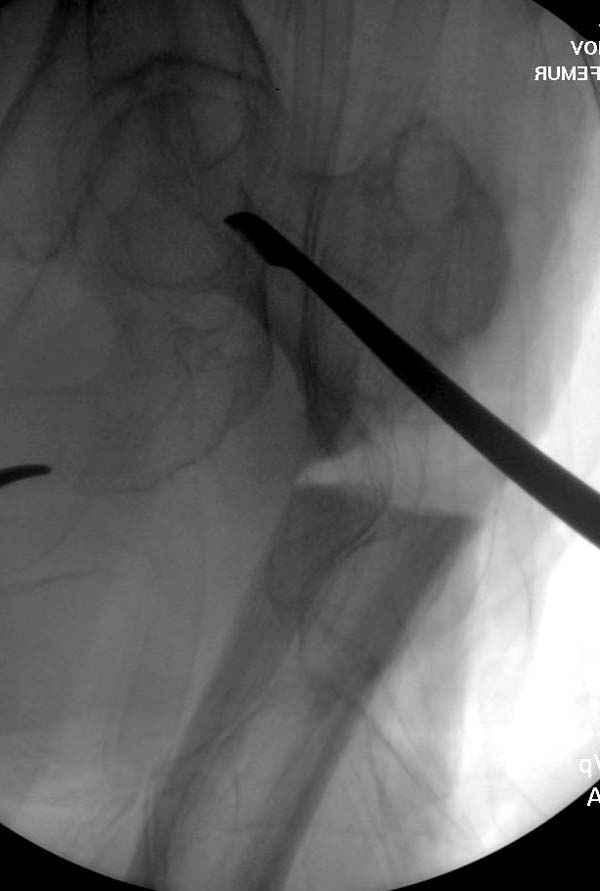

Михаил, здравствуйте. Если присмотреться - на четвертом снимке есть перелом гвоздя по отверстию.

Видимо, проблем тут две: во-1-х, центральный отломок был оставлен в варусно-сгибательной установке, во-2-х, не динамизировали вовремя.

Нижние винты хотели сломаться, но, увы, один не сломался, и тогда сломался гвоздь. Хотя и при динамизации в таком положении отломков

могло не срастись.

Страйкер предоставил отличный инструмент - крючок для удаления длинного гвоздя. Считаем, что врачебная ошибка по установке привела к несостоятельности импланта и к ятрогенному осложнению.